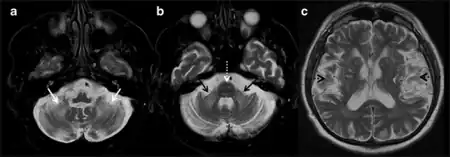

a-c)MRI Fragile X- Associated Tremor/Ataxia Syndrome (FXTAS)

FXTAS can be diagnosed using a combination of molecular, clinical, and radiological findings. In order for individuals to develop FXTAS, they must first be premutation carriers, having between 55 and 200 CGG trinucleotide repeat expansion of the FMR1 gene. A definite, probable, or possible diagnosis of FXTAS can be assigned based on combined clinical or radiological findings in conjunction with the molecular premutation.[10]

Clinical findings are divided into major and minor symptoms. Major symptoms include intention tremor and gait ataxia. Minor symptoms such as parkinsonism, short-term memory deficit, and executive function decline can further contribute to a diagnosis of FXTAS. Radiological findings are similarly divided into major and minor categories. As patients with FXTAS can have distinct brain scans from other movement disorders, a scan showing white matter lesions of the middle cerebellar peduncle is a major finding that can be attributed to FXTAS. Overall or generalized brain tissue atrophy and cerebral white matter lesions can also be minor indicators for a diagnosis.[10]

For a definite diagnosis to be made, a major radiological finding and one major clinical finding must be present. Probable diagnosis is based on the presence of either a major radiological finding and a minor clinical finding, or two major clinical findings alone. The possible category for diagnosis can be made with a minor radiological finding and a major clinical finding.[10]